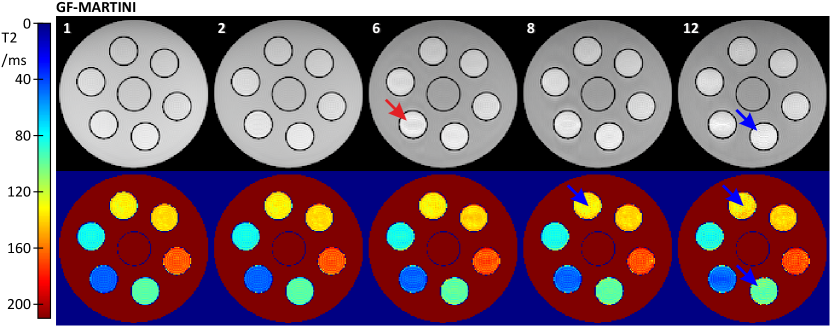

For the relaxation phantom, Fig. 5

demonstrates the results of the proposed GF-MARTINI method ( frequency samples, validity mask, CG iterations) for different degrees of undersampling. Again, effects of the limited oversampling in the frequency domain are most notable only in the spin-density map for the surrounding water compartment. However, this region was successfully identified as invalid after the first optimization block. Apart from that, all other regions are reconstructed with very high accuracy for all undersampling factors. Artifacts are barely notable except for some minor blurring around the compartment with the smallest T2 (red arrow). For undersampling factor greater than , some small vertical ghosts appear, as most notable in compartments and (blue arrows). For all cases a corresponding ROI analysis of T2 values is given in Table II.

The resulting values are remarkably stable with deviations of less than from the fully sampled SE reference for all compartments and undersampling factors.